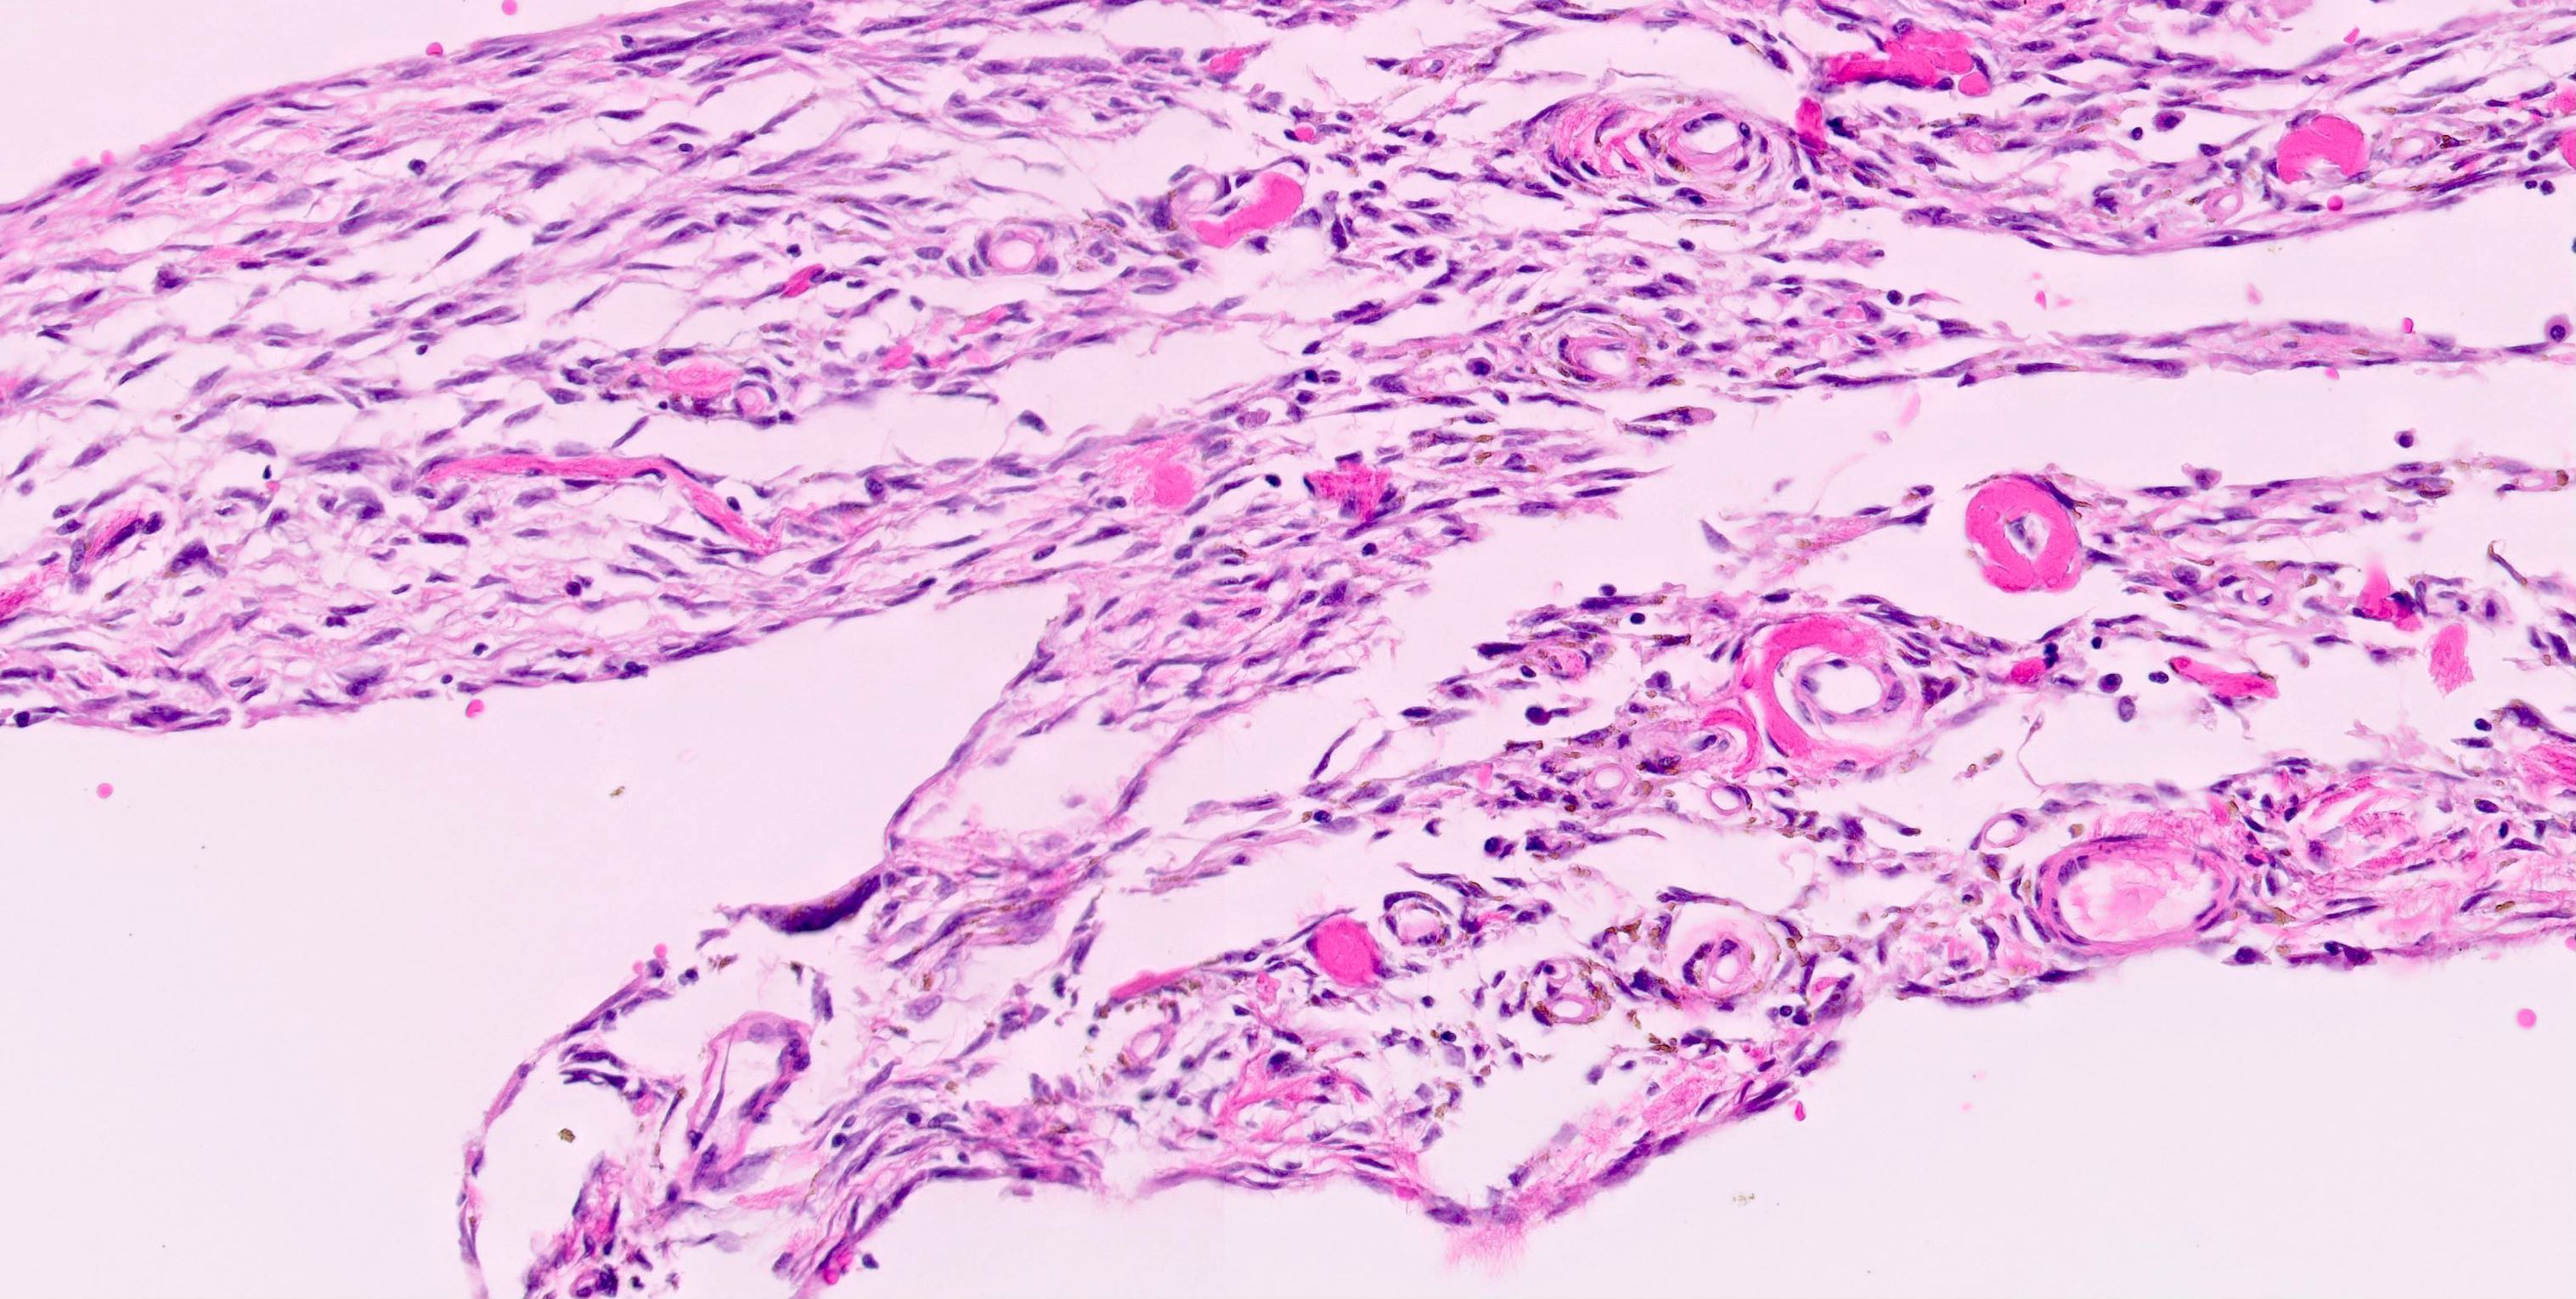

- Highly sensitive (98 - 100%) and specific (100%) nuclear marker for solitary fibrous tumor at all anatomical locations, regardless of tumor morphology (Pathology 2014;46:389, Mod Pathol 2014;27:390, Am J Surg Pathol 2014;38:552)

- NAB2::STAT6 fusion gene acts as activator of EGR1 (early growth response 1) targeted transcription and relocates to the nucleus, with resultant strong nuclear expression of STAT6 by immunohistochemistry (Mod Pathol 2014;27:390, Am J Clin Pathol 2015;143:672)

- Nuclear stain

- Solitary fibrous tumor (98 - 100%), regardless of morphology or site, typically strong and diffuse (Pathology 2014;46:389, Pediatr Dev Pathol 2018;21:389, Acta Neuropathol 2013;125:651)